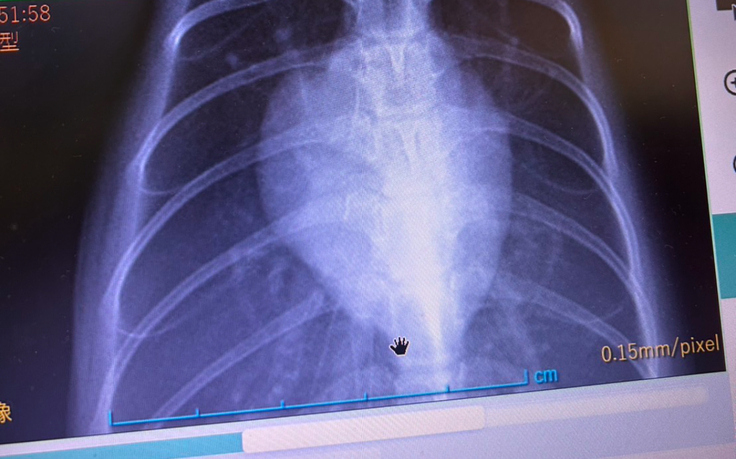

先日、定期的な通院で検査してもらったところ、

心肥大と心臓弁膜症が発覚しました…